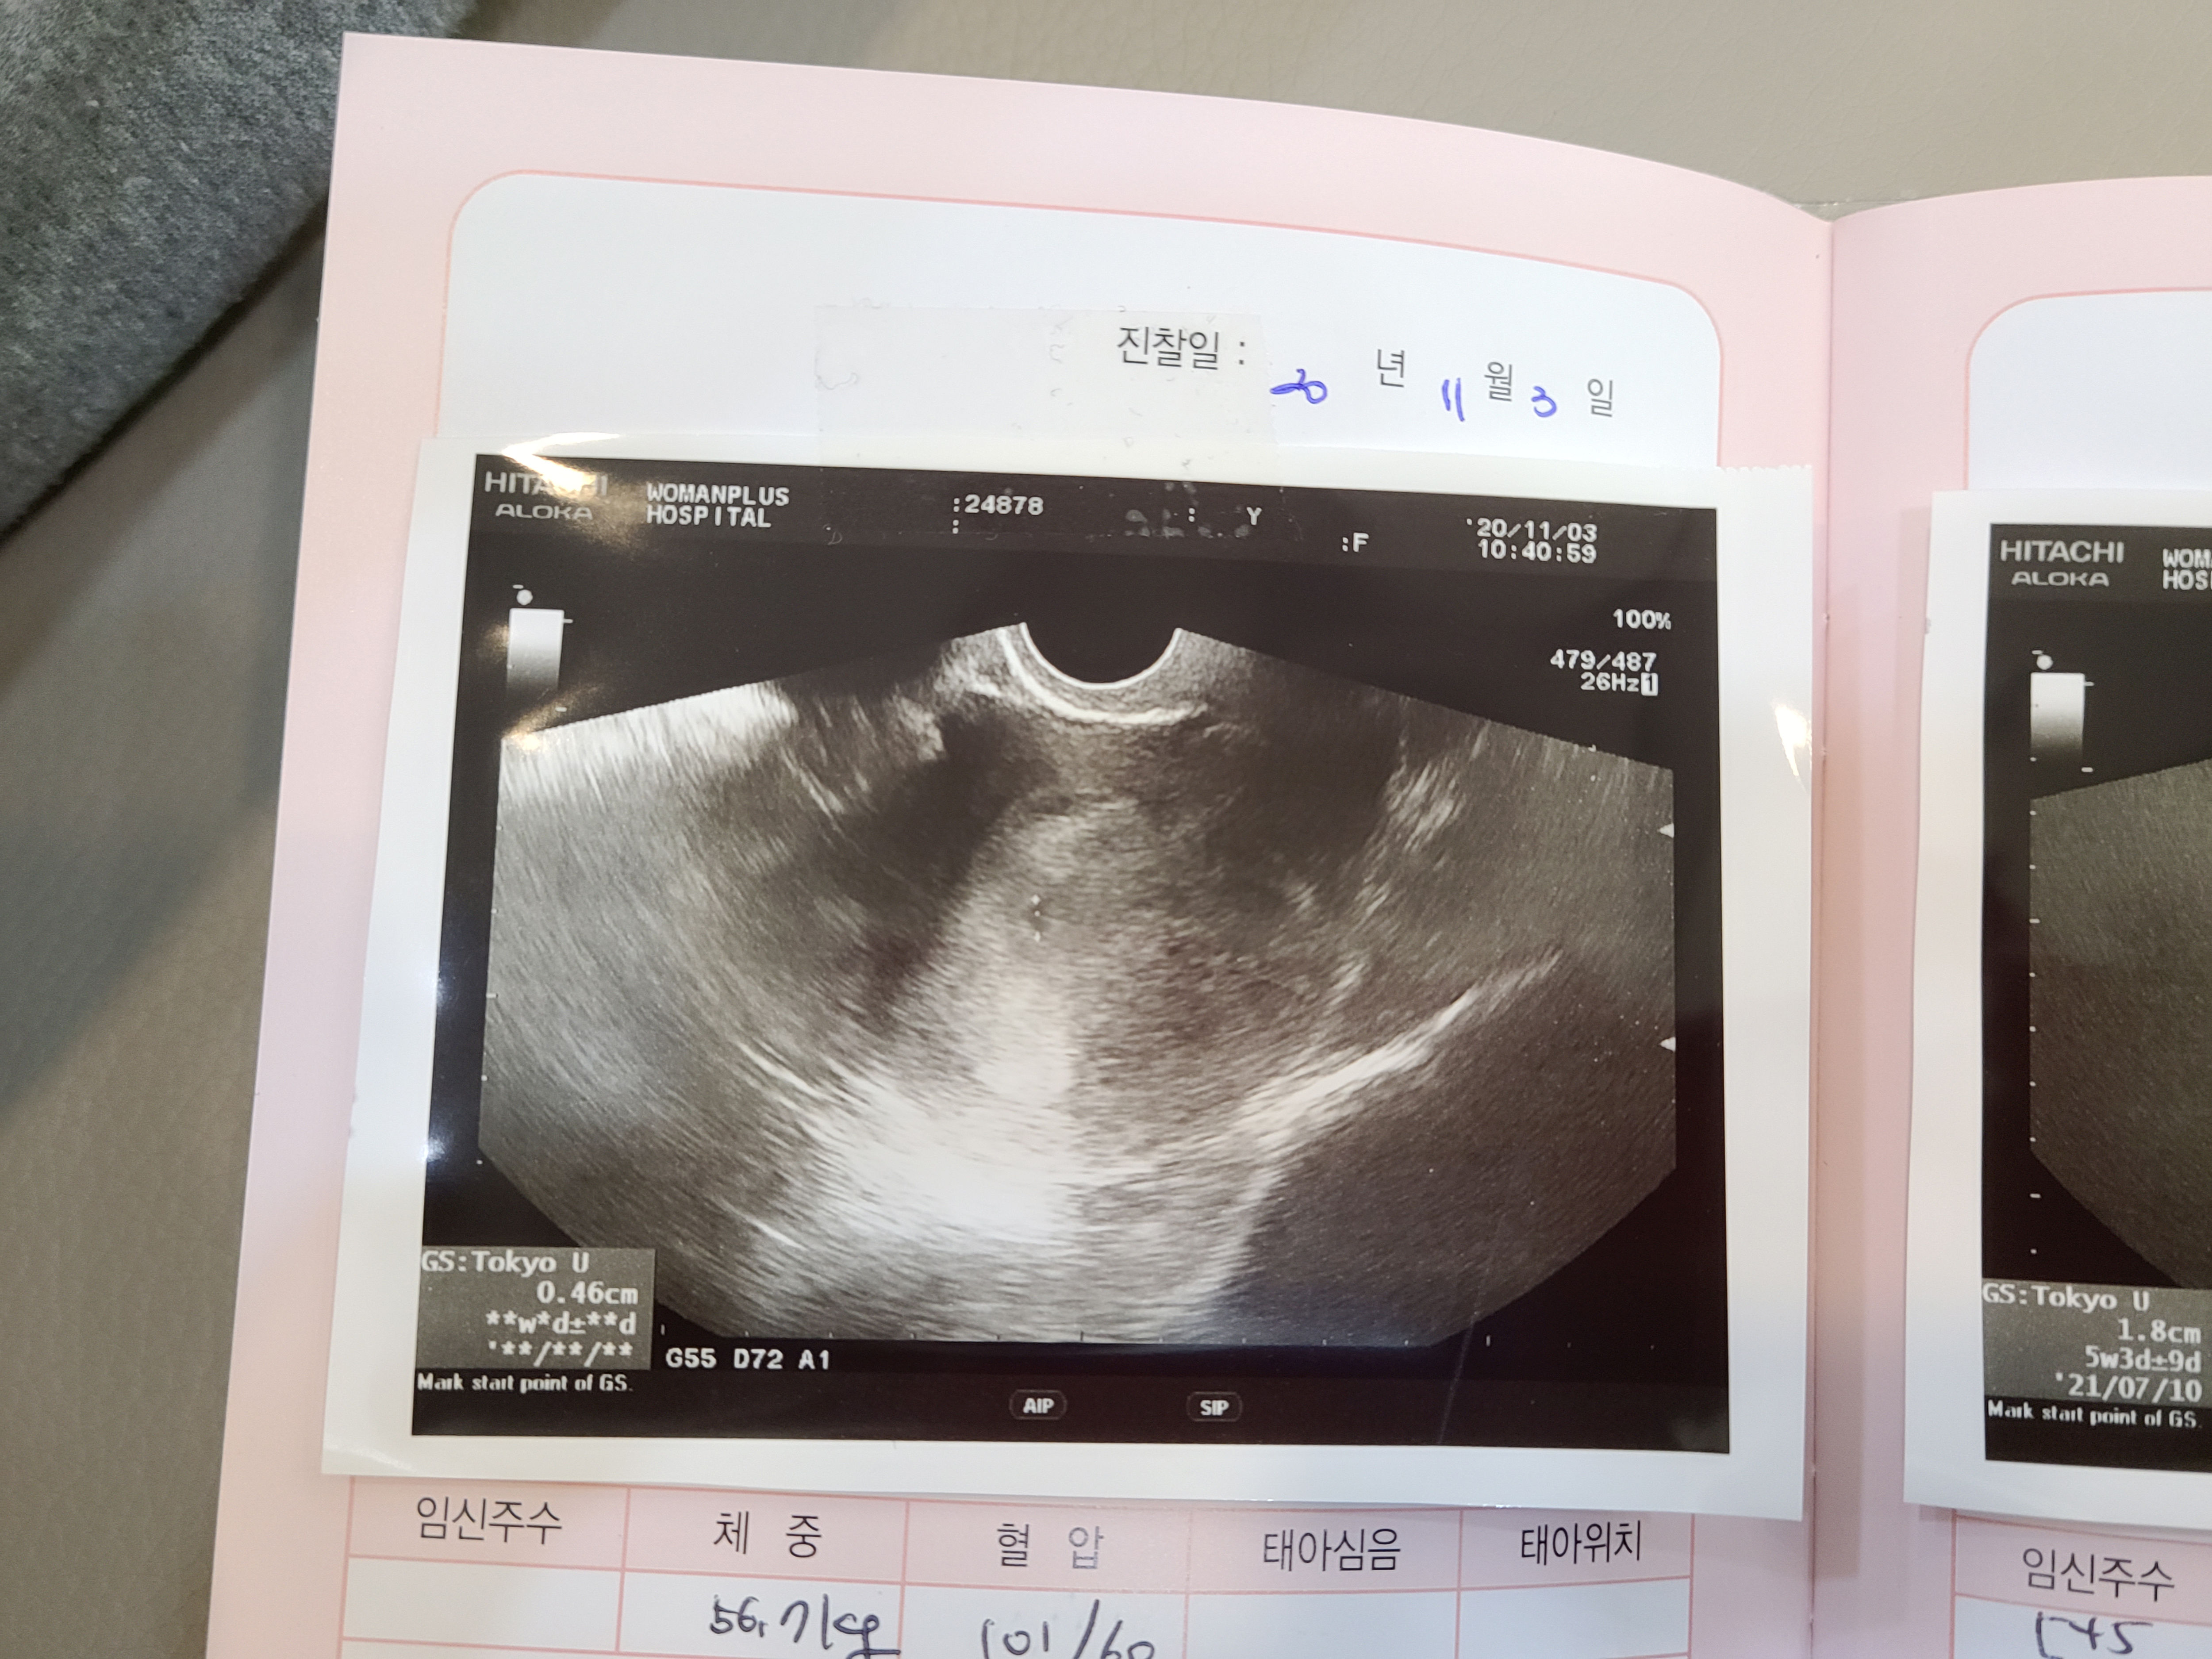

처음 너는 세포 분열 중이였어.